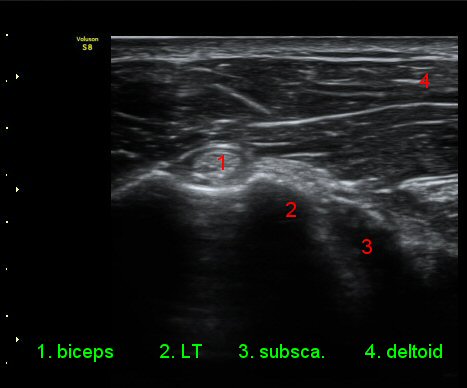

ÃÊÀ½ÆÄ °Ë»ç

ÀÌµÎ¹Ú±Ù°Ç È¾´Ü¸é°Ë»ç¿¡¼­ °ÇÁÖÀ§¿¡ ¼Ò·®ÀÇ ¼ö¾×Àú·ù¿Í Á¡¾×³¶³» ¾×Àú·ù°¡ °üÂûµÈ´Ù(»çÁø 1, 2).